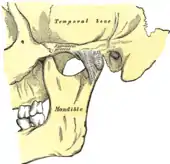

![]() | |

Temporomandibular joint | |

Temporomandibular joints

The temporomandibular joints are the dual articulation of the mandible with the skull. Each TMJ is classed as a "ginglymoarthrodial" joint since it is both a ginglymus (hinging joint) and an arthrodial (sliding) joint,[41] and involves the condylar process of the mandible below, and the articular fossa (or glenoid fossa) of the temporal bone above. Between these articular surfaces is the articular disc (or meniscus), which is a biconcave, transversely oval disc composed of dense fibrous connective tissue. Each TMJ is covered by a fibrous capsule. There are tight fibers connecting the mandible to the disc, and loose fibers which connect the disc to the temporal bone, meaning there are in effect 2 joint capsules, creating an upper joint space and a lower joint space, with the articular disc in between. The synovial membrane of the TMJ lines the inside of the fibrous capsule apart from the articular surfaces and the disc. This membrane secretes synovial fluid, which is both a lubricant to fill the joint spaces, and a means to convey nutrients to the tissues inside the joint. Behind the disc is loose vascular tissue termed the "bilaminar region" which serves as a posterior attachment for the disc and also fills with blood to fill the space created when the head of the condyle translates down the articular eminence.[42] Due to its concave shape, sometimes the articular disc is described as having an anterior band, intermediate zone and a posterior band.[43] When the mouth is opened, the initial movement of the mandibular condyle is rotational, and this involves mainly the lower joint space, and when the mouth is opened further, the movement of the condyle is translational, involving mainly the upper joint space.[44] This translation movement is achieved by the condylar head sliding down the articular eminence, which constitutes the front border of the articular fossa.[35] The function of the articular eminence is to limit the forwards movement of the condyle.[35] The ligament directly associated with the TMJ is the temporomandibular ligament, also termed the lateral ligament, which really is a thickening of the lateral aspect of the fibrous capsule.[35] The stylomandibular ligament and the sphenomandibular ligament are not directly associated with the joint capsule. Together, these ligaments act to restrict the extreme movements of the joint.[45]